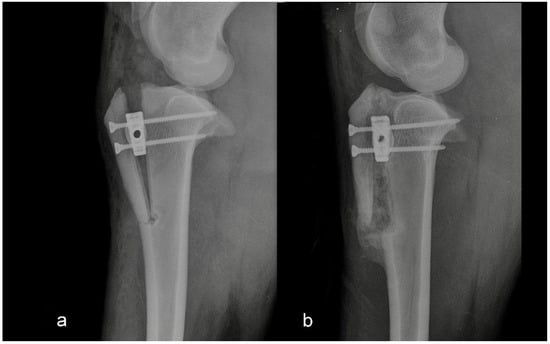

The second group consisted of five sheep in which the intraoperative or postoperative discrepancies from preoperative planning were found. Discrepancies were either the osteotomy line was too close to the tibial crest, or the tibial crest was cracked at the level of the Maquet hole (Figure 2 and Figure 3).

Figure 3. Mediolateral radiograph of the stifle in Group 2 immediately postoperatively (a) and at six months postoperatively (b). The osteotomy line was too close to the tibial tuberosity crest.